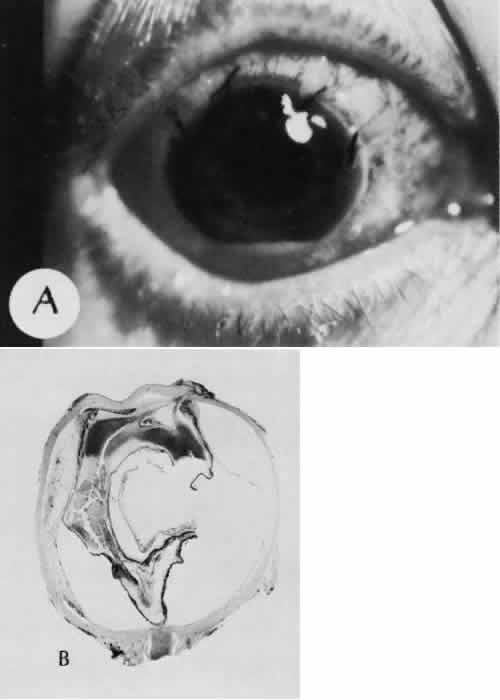

Iris or lens capsular incarceration into the wound and extending to the conjunctival space (Figs. 32 and 33) may act as a wick through which aqueous can escape, causing a flat anterior chamber. Histologically, iris, which is frequently recognized only by the presence of melanocytes, is seen in the limbal scar, in the limbal episclera, or in both areas.

Fig. 32. A case of retinal detachment. A. In this case, the iris has become incarcerated into a limbal wound. A series of events leads to total retinal detachment (morning glory detachment). The presence of multiple areas of macrocystic degeneration of the detached retina indicates that the situation is chronic and probably not repairable. B. The histologic section of this case indicates the extent of iris incarceration and the fragility of the wound. (Hematoxylin-eosin stain; × 40.)

Fig. 33. A case of iris prolapse through a limbal wound. A. A large black mass has appeared at the limbus of a patient with a history of cataract extraction. There may or may not be a history of trauma or Valsalva maneuver. The differential diagnosis at first glance would certainly include primary conjunctival malignant melanoma or extraocular extension of a primary uveal malignant melanoma. A major differential observation from iris prolapse is the character and degree of alteration of the iris tissue remaining within the eye. B. By histologic section no cellular mass is present either in the episcleral or uveal tissue. The remaining iris is stretched and adherent to the posterior corneal surface. (Hematoxylin-eosin stain; × 40.)